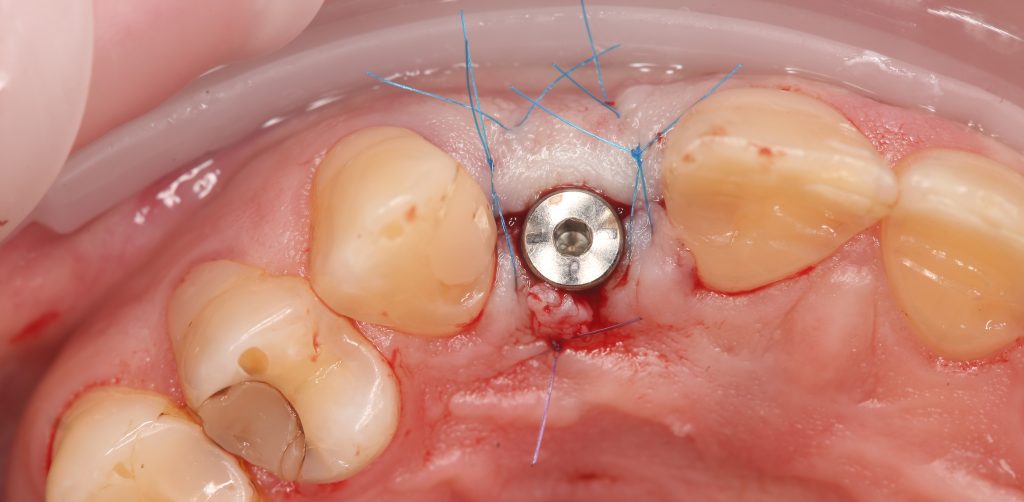

Хирургический этап имплантологического лечения